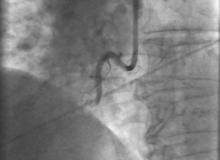

Canada is spearheading an international study to determine if an implantable cardioverter defibrillator (ICD) can prevent death from serious heart rhythm problems in those patients who’ve survived a heart attack. Heart disease is a leading cause of death in Canada and the fastest growing disease worldwide.